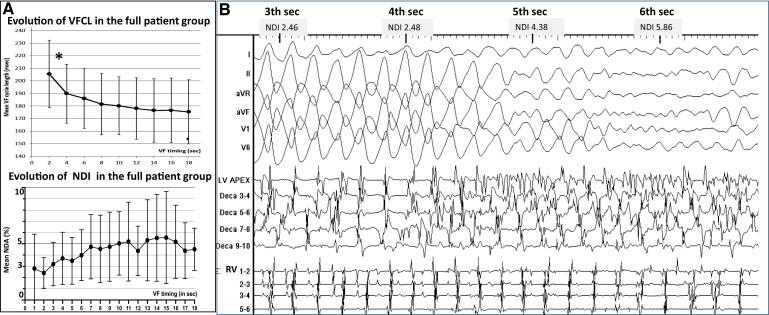

We evaluated 54 patients (50 ± 16 years) with VF in the setting of ischaemic (n = 15), hypertrophic (n = 8) or dilated cardiomyopathy (n = 12), or Brugada syndrome (n = 19). Ventricular fibrillation was mapped using body-surface mapping to identify driver (reentrant and focal) areas and invasive Purkinje mapping. Purkinje drivers were defined as Purkinje activities faster than the local ventricular rate. Structural substrate was delineated by electrogram criteria and by imaging. Catheter ablation was performed in 41 patients with recurrent VF. Sixty-one episodes of spontaneous (n = 10) or induced (n = 51) VF were mapped. Ventricular fibrillation was organized for the initial 5.0 ± 3.4 s, exhibiting large wavefronts with similar cycle lengths (CLs) across both ventricles (197 ± 23 vs. 196 ± 22 ms, P = 0.9). Most drivers (81%) originated from areas associated with the structural substrate. The Purkinje system was implicated as a trigger or driver in 43% of patients with cardiomyopathy. The transition to disorganized VF was associated with the acceleration of initial reentrant activities (CL shortening from 187 ± 17 to 175 ± 20 ms, P < 0.001), then spatial dissemination of drivers. Purkinje and substrate ablation resulted in the reduction of VF recurrences from a pre-procedural median of seven episodes [interquartile range (IQR) 4-16] to 0 episode (IQR 0-2) (P < 0.001) at 56 ± 30 months.

我们评估了 54 名 VF 患者(50±16 岁),其中缺血性(n=15)、肥厚性(n=8)或扩张型心肌病(n=12)或 Brugada 综合征(n=19)。使用体表标测确定驱动区(折返和局灶性),采用心外膜标测和侵入性浦肯野纤维标测来确定浦肯野纤维驱动区。浦肯野纤维驱动区定义为比局部心室率快的浦肯野纤维活动。采用电描记图标准和影像学来确定结构性基质。在 41 名复发性 VF 患者中进行了导管消融。对 61 次自发性(n=10)或诱发性(n=51)VF 发作进行了标测。VF 的初始持续时间为 5.0±3.4s,表现为具有相似的周期长度(CL)的大波前,左右心室均相似(197±23 与 196±22ms,P=0.9)。大多数驱动区(81%)起源于与结构性基质相关的区域。浦肯野系统在 43%的心肌病患者中被认为是触发或驱动因素。从最初的折返活动加速(CL 从 187±17 缩短至 175±20ms,P<0.001)到随后的驱动区空间传播,与无序 VF 的发生相关。浦肯野纤维和基质消融使 VF 复发从术前中位数的 7 次(IQR 4-16)减少至 0 次(IQR 0-2)(P<0.001),随访 56±30 个月。